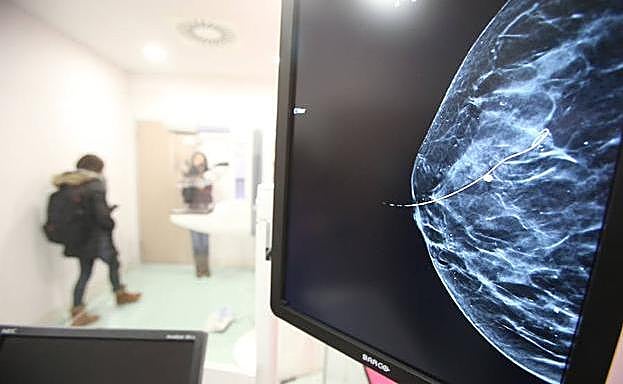

Imagen de una mamografía.